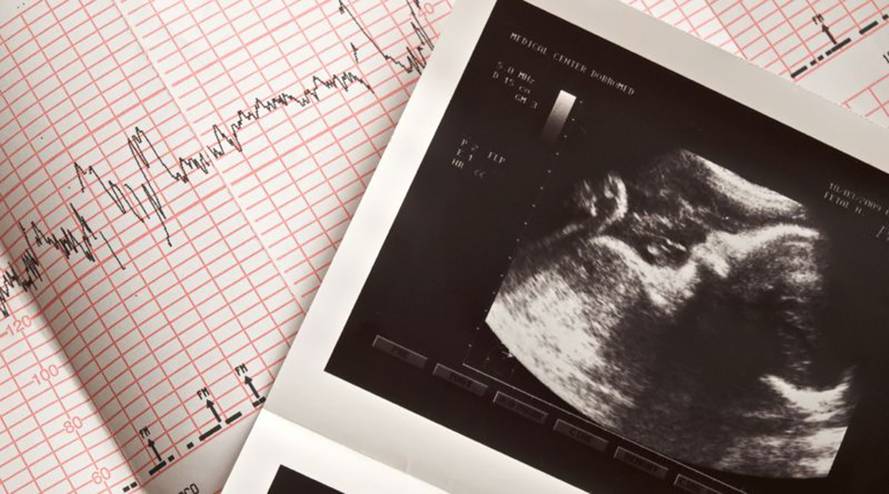

Das Ersttrimesterscreening, auch First-Trimester-Screening genannt, dient dazu Chromosomenanomalien wie z. B. das Down-Syndrom beim Ungeborenen zu entdecken.

Das Ersttrimesterscreening findet zwischen der elften und 13. Schwangerschaftswoche statt und ist eine Kombinationsuntersuchung, bei der verschiedene Werte untersucht werden, um eine Risikowahrscheinlichkeit zu berechnen. Die Untersuchung besteht aus einer Nackenfaltenmessung und einem Bluttest, bei dem zwei Werte des mütterlichen Blutes kontrolliert werden: PAPP-A* und freies β-hCG**. Um eine Aussage darüber treffen zu können, mit welcher Wahrscheinlichkeit das Kind mit einer Anomalie auf die Welt kommen würde, werden neben den Untersuchungsergebnissen der Nackenfaltenuntersuchung sowie des Blutes, das Alter der Mutter einberechnet. Jedoch handelt es sich bei dieser Untersuchung um eine Wahrscheinlichkeitsangabe und um keine genaue Diagnose. Ein annähernd eindeutiges Ergebnis kann jedoch nur durch ein invasives Verfahren wie eine Fruchtwasseruntersuchung erreicht werden. Das Ersttrimesterscreening müssen die Eltern aus eigener Tasche bezahlen, da es nicht in den Mutterschaftsrichtlinien vorgesehen ist.